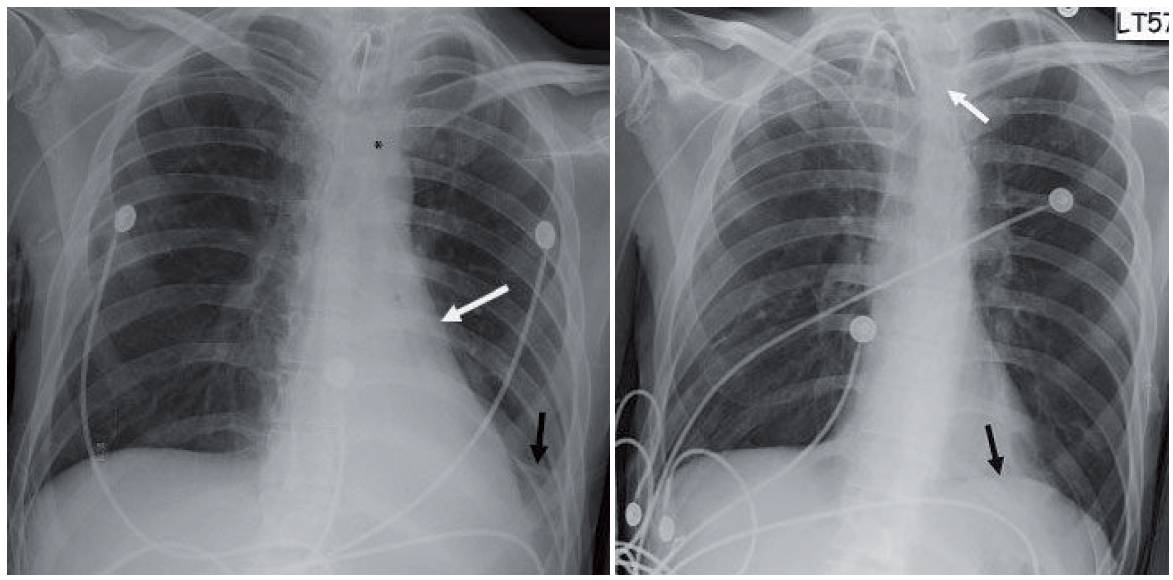

- Initial chest radiograph (first image) shows a retrocardiac opacity with air bronchograms and narrowed distances between the left ribs. The left hemidiaphragm cannot be seen behind the heart and the left heart border appears straightened. Also note the inferior location of the left hilum.

- The altered left heart border appears straighter than normal. This finding has been referred to as the flat waist sign (white arrow in first image).

- Lingular linear atelectasis is another finding in left lower lobe collapse (Nordentsrom’s sign). This comes from the altered orientation of the lingular bronchi with hyperexpansion (black arrow in first image).

- Two other findings of left lower lobe collapse include shift of the anterior junction line and the top of the knob sign. In the latter, shifted mediastinal soft tissues obscure the top of the aortic arch (asterisk in first image).